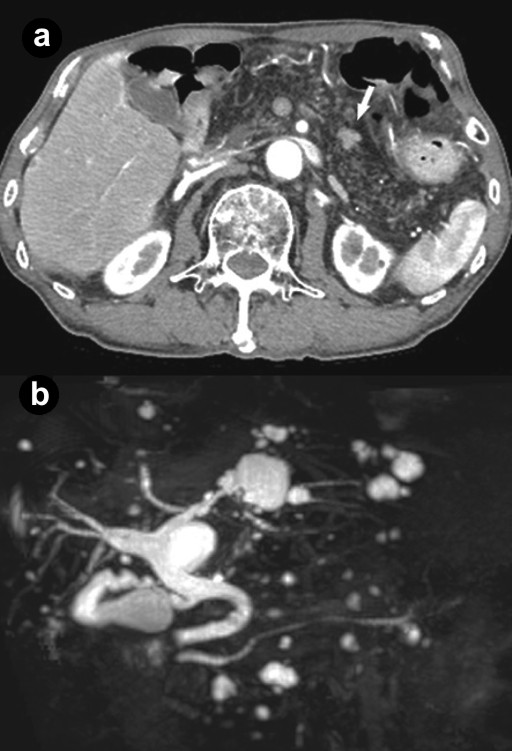

Figure 1. a. Abdominal dynamic computed tomography showed a slightly enhanced early phase 10 mm mass (arrow) in the pancreatic body, diffuse fat density, and net-like shadow in the entire pancreas. b. Magnetic resonance cholangiopancreatography demonstrated no abnormal findings, such as obstruction, narrowing or dilatation in the main pancreatic duct or multiple hepatic and pancreatic cysts. |